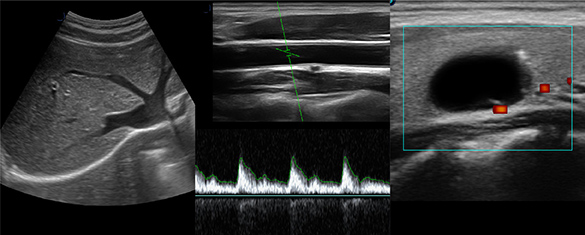

Confident Diagnosis in General Imaging

DS20 is a preferred compact ultrasound platform for today’s general imaging challenges. It delivers advanced solutions across a wide range of clinical applications, providing excellent image quality for both routine examinations and detailed evaluations in daily practice.

High-Quality Imaging Across Applications

Provides reliable diagnostic imaging across a wide range of clinical fields including abdomen, cardiology, thyroid, vascular, breast, and musculoskeletal examinations.